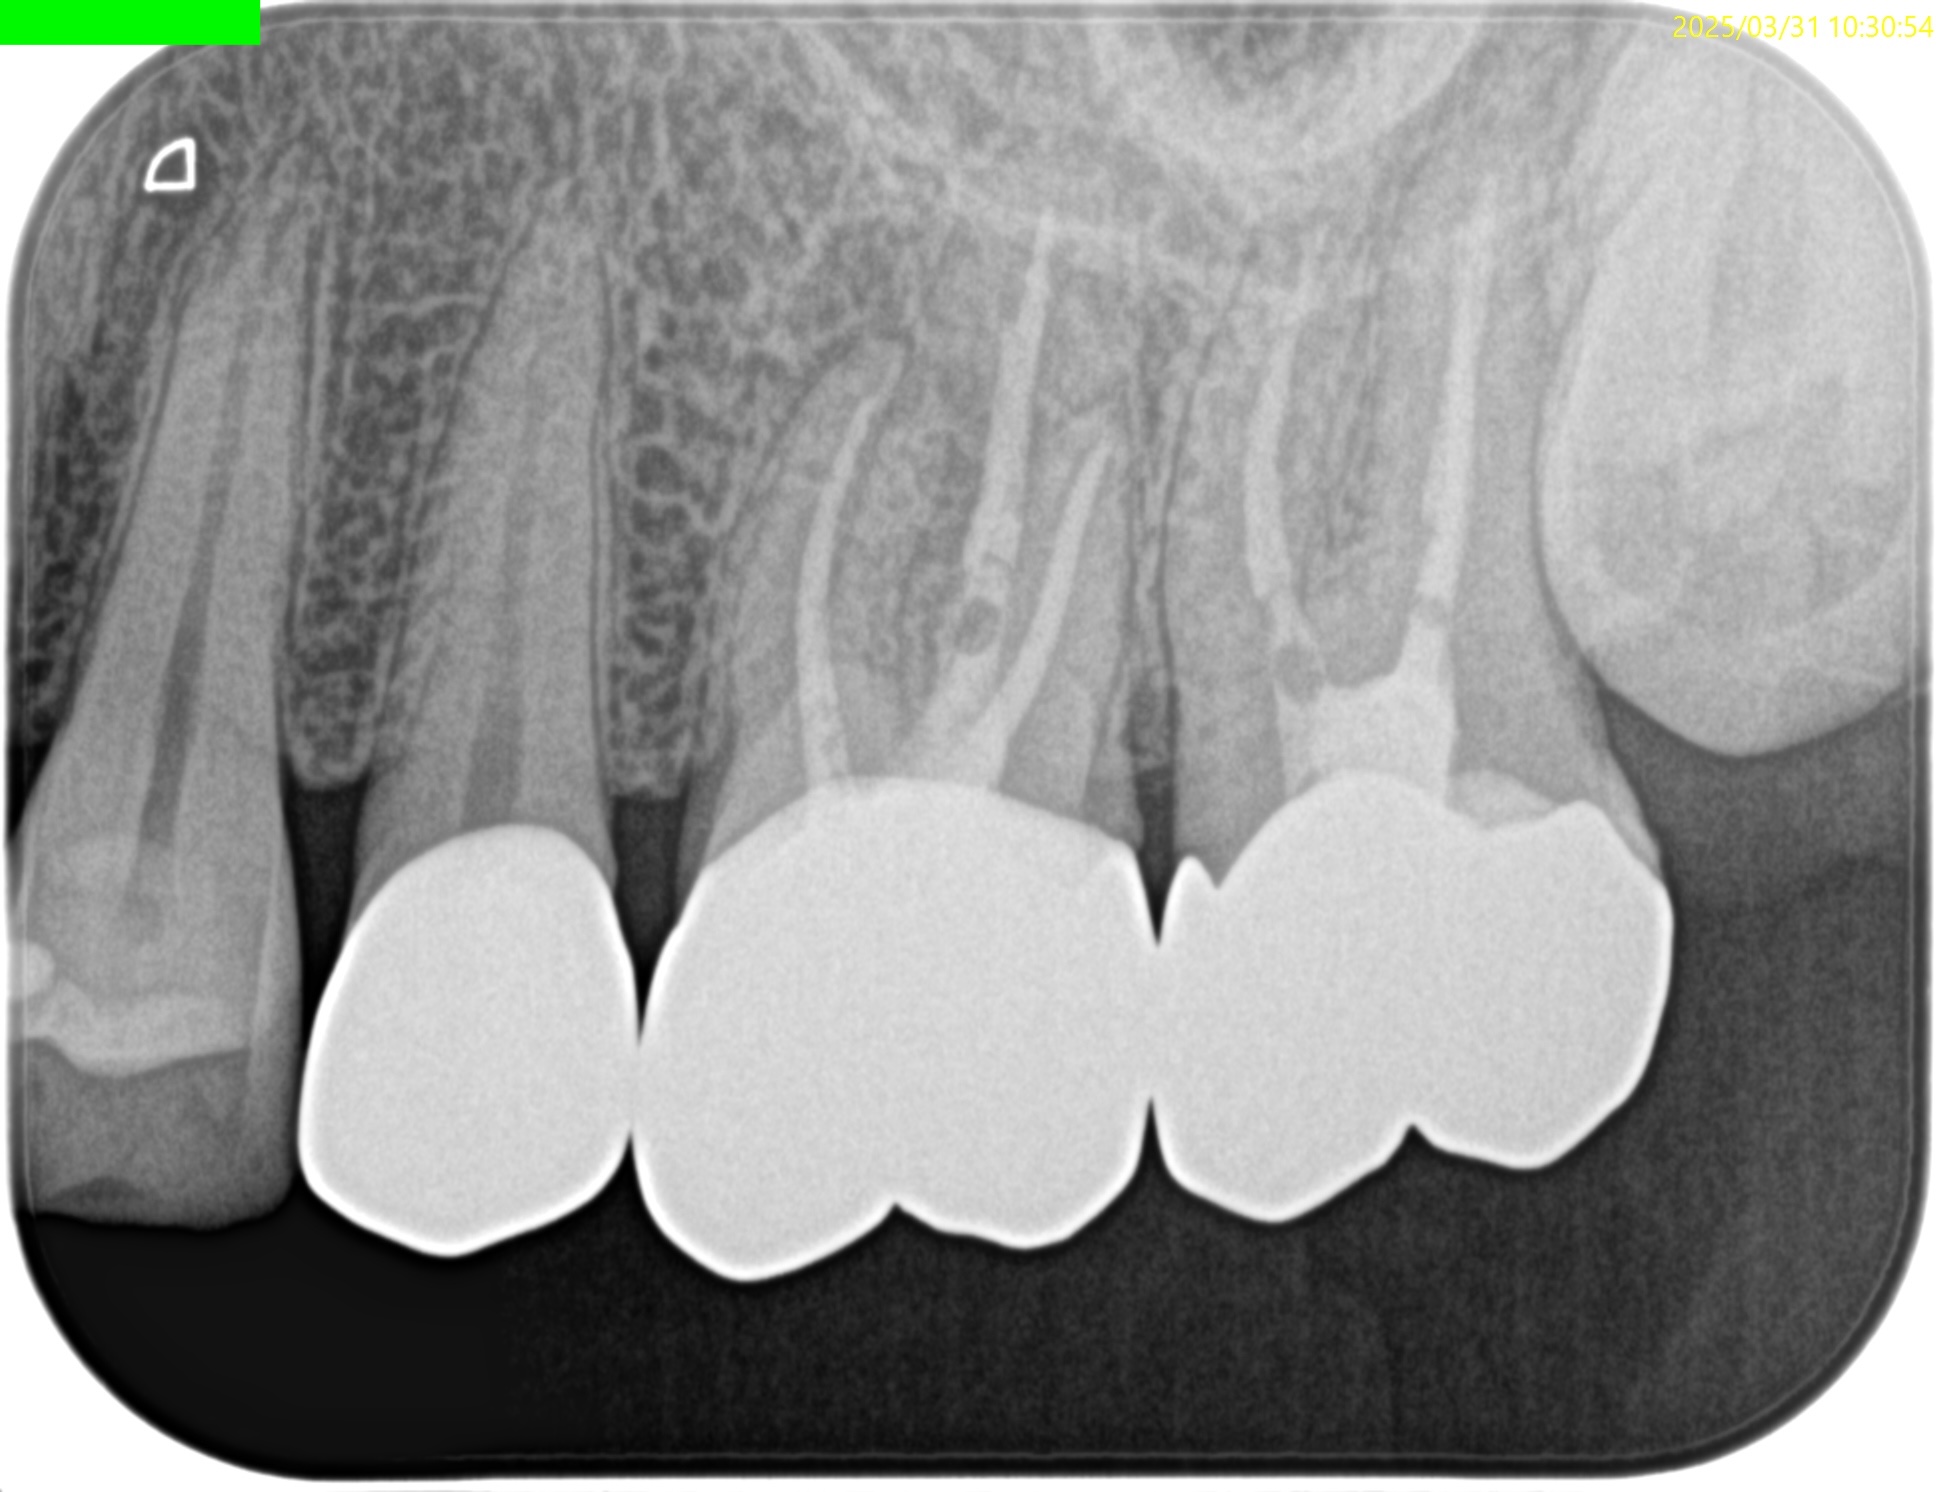

Pre-op Endo test(2025.3.31)

MB

DB

P

MBに大きな病変がある。DB,Pには病変はない。

これが検査での圧痛の原因だろう。

またすでに必要十分に拡大形成がなされていること,

MBの中央にGutta Percha Pointがあることから、MB2はなくMB1のみの処置でいいとわかるところもCBCTの強みである。